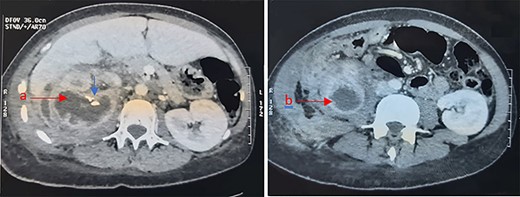

An abdominal computed tomography (CT) scan revealed an obstructive right staghorn calculus measuring 27 mm with homolateral hydronephrosis and infiltration of perirenal fat. Renal and para renal multilocular collections were described: one pararenal collection measuring 50 mm, a second collection was located in the right paracolic gutter and measuring 23 × 20 mm. An exophytic multilocular renal collection was also described, with calcifications and well-defined wall measuring 67 mm (Fig. 1).

Abdominal CT showing a right renal multilocular collection, measuring 67 mm (a) with calcifications (Blue arrow) and a right para renal collection measuring 50 mm (b).